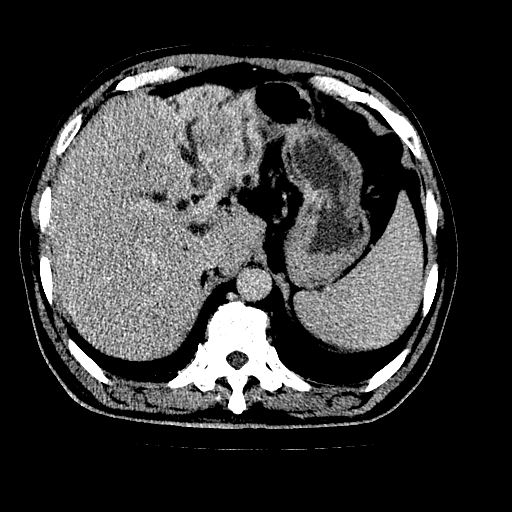

男,66岁,上腹部不适、黄染一周。彩超示:肝左叶占位,肝内胆管扩张,胆总管扩张,胆总管占位?

肝左叶不规则软组织肿块影,边缘不规整邻近肝实质受累分界不清;肝内胆管(左叶)明显扩张成“软藤状”,诊断:肝左叶胆管细胞癌。

肝左叶占位性病变,并胆管扩张,符合胆管细胞癌ct表现,门脉左支受累,左肾囊肿。窗宽太窄了,其他的看不清

左叶胆管细胞癌累及胆总管,门脉左支受侵,慢性胆囊炎胆结石,左肾小囊肿

肝左叶不规则软组织肿块影,边缘不规整邻近肝实质受累分界不清;肝内胆管(左叶)明显扩张成“软藤状”,诊断:肝左叶胆管细胞癌。胆囊钙乳症。